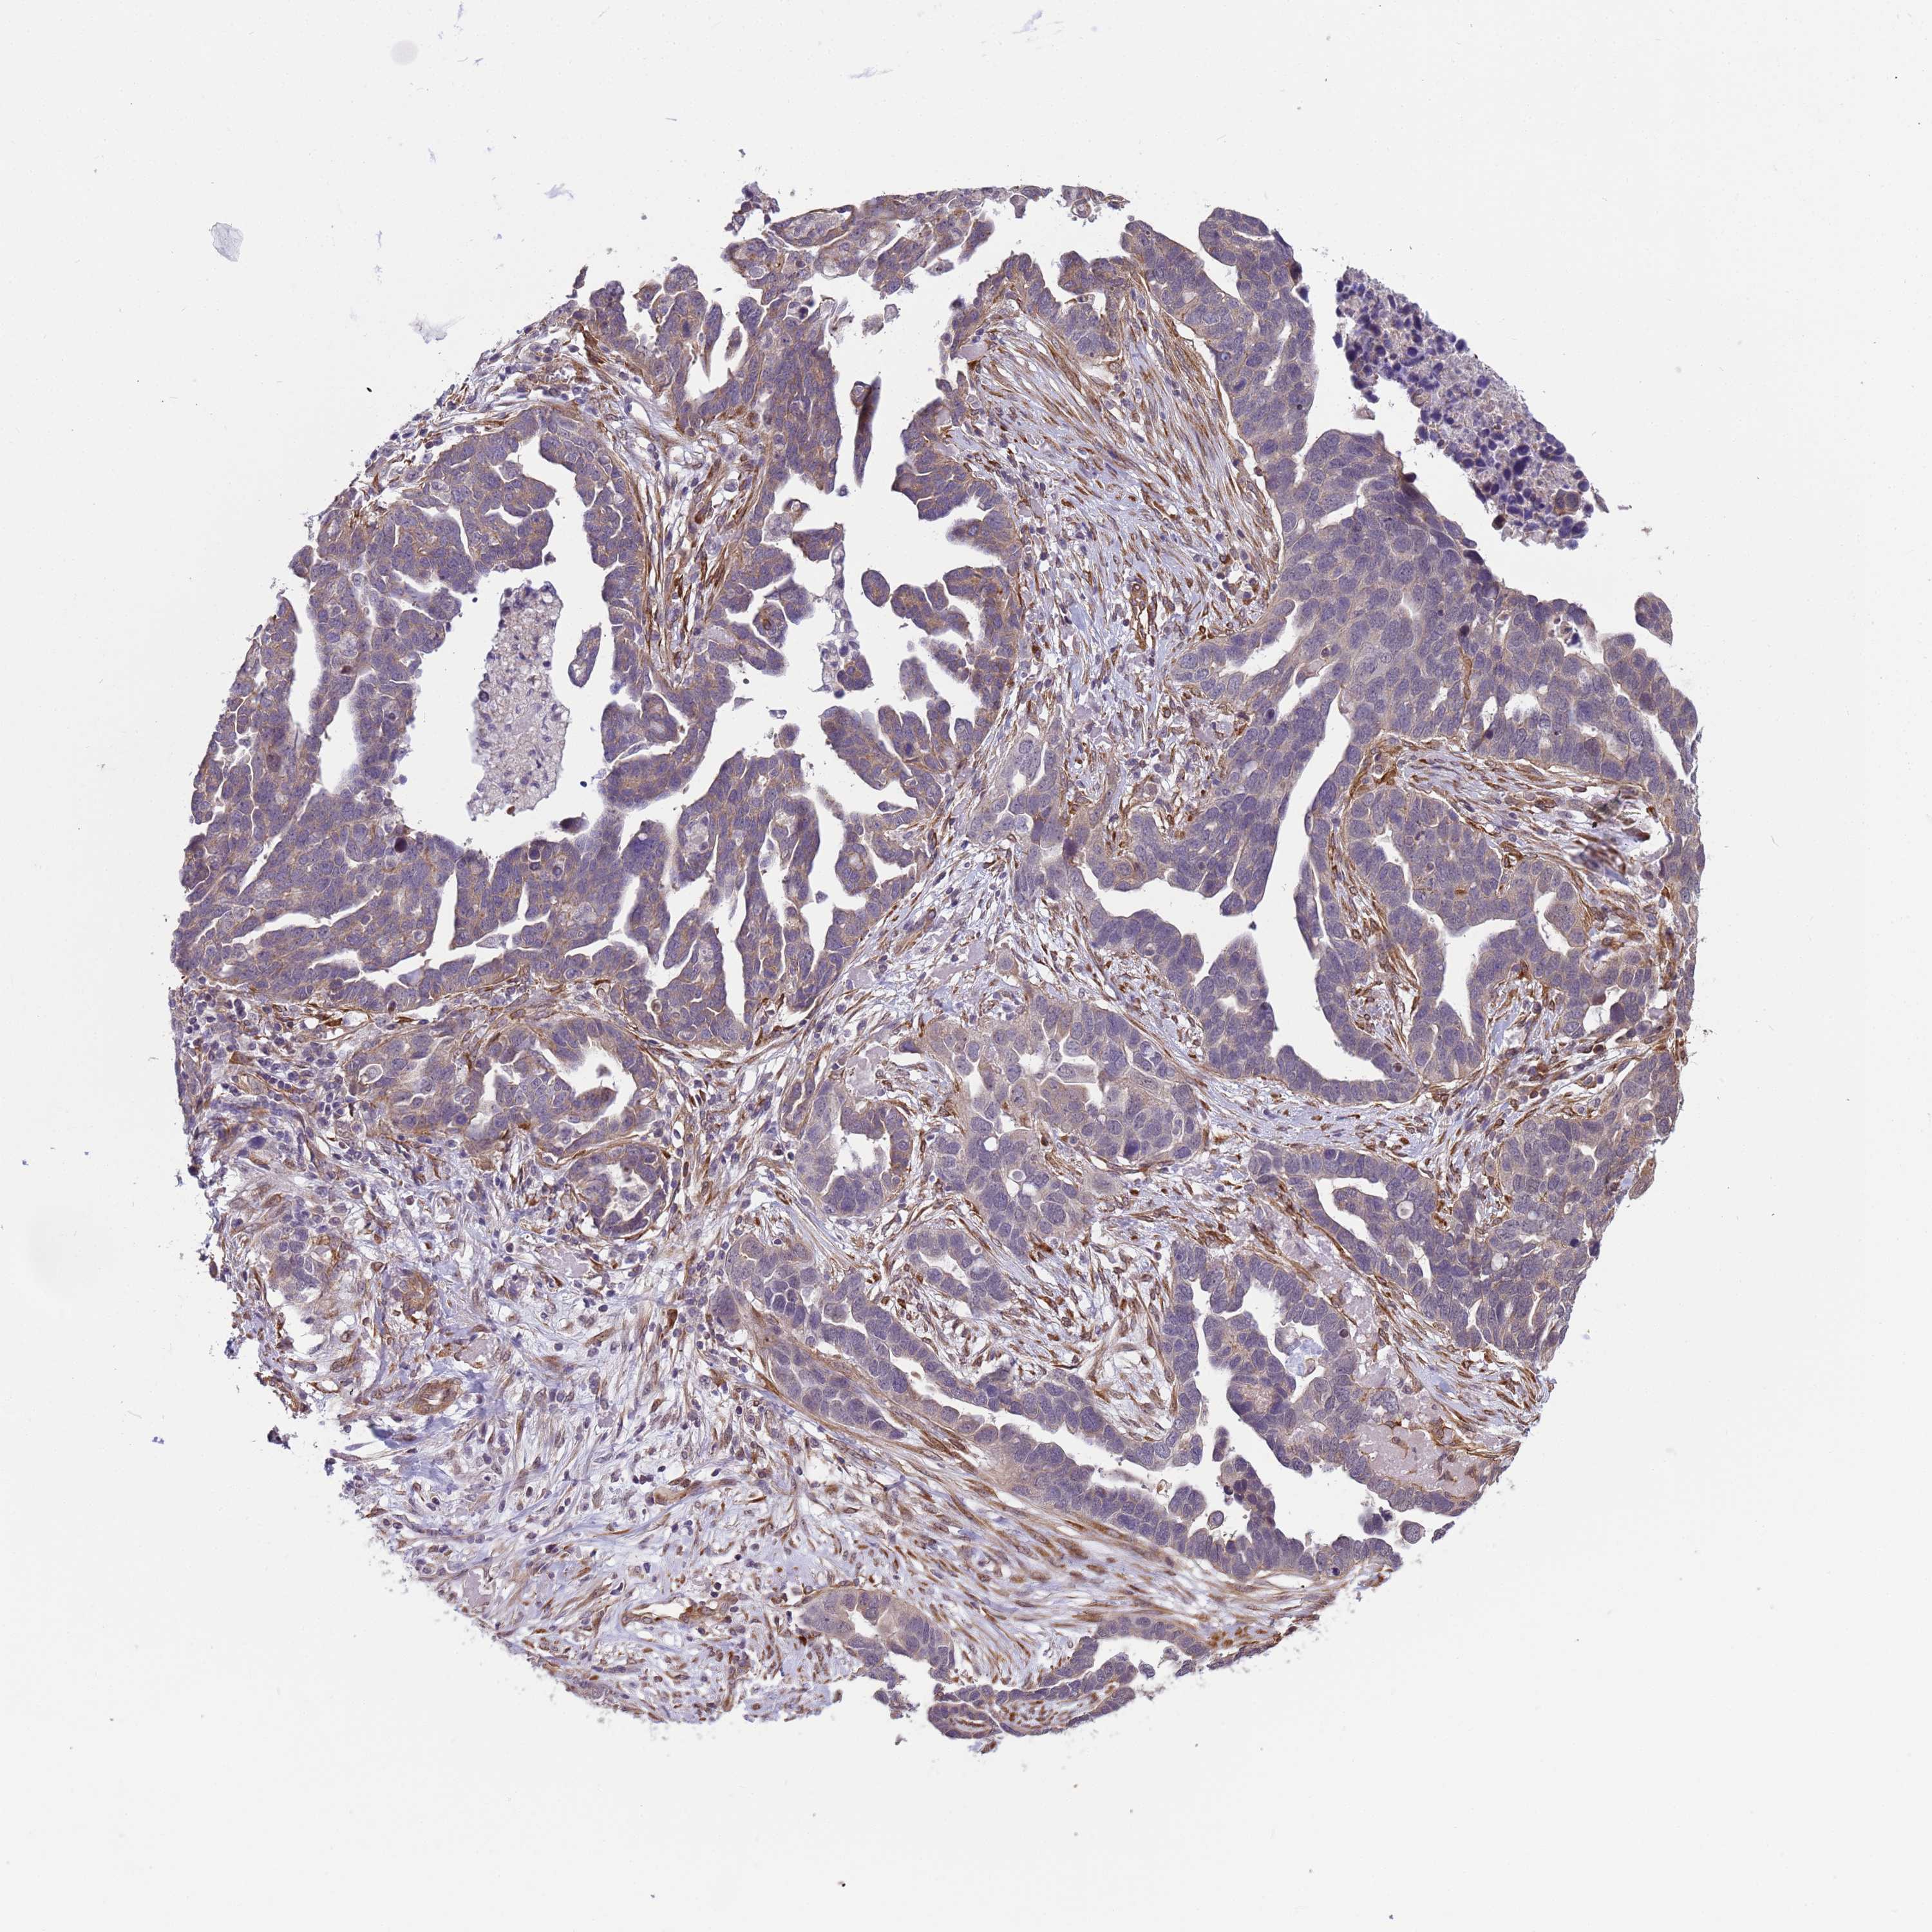

OVARIAN CANCER - Protein expressioni

A mouse-over function shows sample information and annotation data. Click on an image to view it in a full screen mode. Samples can be filtered based on level of antibody staining by selecting one or several of the following categories: high, medium, low and not detected. The assay and annotation is described here.

Note that samples used for immunohistochemistry by the Human Protein Atlas do not correspond to samples in the TCGA dataset.

Antibody stainingi

Antibody staining in the annotated cell types in the current human tissue is reported as not detected, low, medium, or high, based on conventional immunohistochemistry profiling in selected tissues. This score is based on the combination of the staining intensity and fraction of stained cells.

Each image is clickable and will lead to virtual microscopy that enables deeper exploration of all samples and also displays staining intensity scores, fraction scores and subcellular localization as well as patient and tissue information for each sample.

Antibody HPA036348

Antibody HPA036349

Antibody CAB002422

Antibody CAB005258

Cystadenocarcinoma, serous, NOS

Carcinoma, NOS

Cystadenocarcinoma, mucinous, NOS

Carcinoma, endometroid